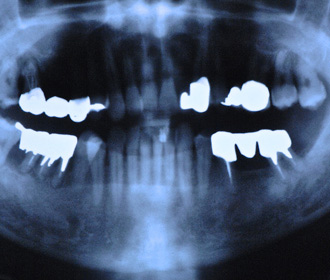

外傷による上顎左右11抜歯後即時インプラント+インビザライン矯正

インプラント治療時にはチタンメッシュ+人工骨による大掛かりな骨移植を行っている。

矯正治療、骨移植を伴うインプラント治療、セラミック・クラウン等による機能的、審美的治療

矯正治療、骨移植を伴うインプラント治療、セラミック・クラウン等による機能的、審美的治療

術前